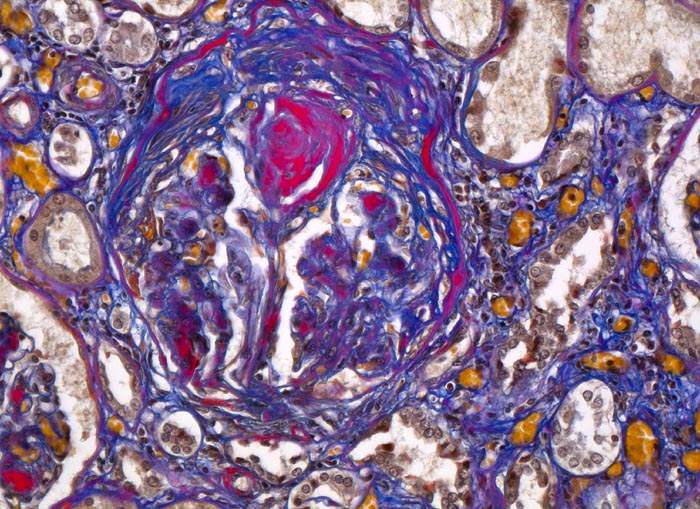

PathoPic ID 4636 - Diabetische noduläre Glomerulosklerose Kimmelstiel-Wilson

Diabetische noduläre Glomerulosklerose Kimmelstiel-Wilson

Partiell verödetes Glomerulum mit

zwiebelschalenartig geschichtetem mesangialem Knoten. Interstitielle Fibrose.

Diabetes mellitus Typ II seit 20 Jahren.

Vergrösserung

200